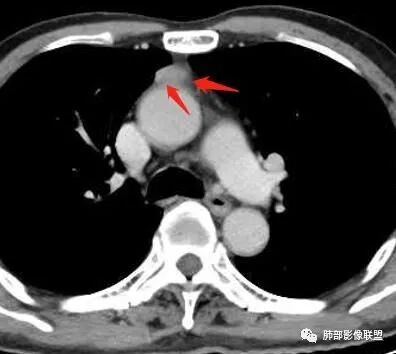

秦化君:前纵隔结节影,边缘清晰光整,质软,密度较均匀。增强较明显强化。考虑前纵隔良性病变,胸腺瘤?纵隔窗第一层面病灶内似有低密度,畸胎瘤待除外。

༺༽༾ཊ天涯ཏ༿༼༻꧂:前纵隔,边缘光整,密度较均匀,强化较明显,胸腺瘤?淋巴结?大雄:胸腺或支气管源性囊肿。增强CT值是增加了,但不一定是强化,病灶太小,后方主动脉强化有容积效应。边缘比较平直。三生石上:前纵隔占位,边缘光整,密度较均匀,有明显强化,考虑胸腺瘤。

徐飞:前纵隔结节边缘光滑,与周围脂肪间隙比较有膨隆感,说明结节不是特别软,强化,考虑胸腺瘤。

崇军:老年男性,前纵隔占位,边缘光整,密度较均匀,有明显强化,考虑胸腺瘤。市医院--时建文:前纵隔,边缘光整,密度较均匀,强化较明显,胸腺瘤?

红星:前纵隔大血管前间隙占位,边缘光整,密度较均匀,有明显强化,结合年龄段,考虑胸腺瘤。

Yiren  Sishui(厶水伊人):前纵隔结节,边缘光整,密度较均匀,中度强化,考虑胸腺瘤。

宇宙:前纵隔正中软组织结节,边缘光整, 与血管脂肪间隙欠清,中度强化,似有条状低密度影,考虑低危胸腺瘤,鉴别胸腺囊肿,胸腺增生结节。巴伟:前纵隔胸腺区结节,边缘平直,测量有强化,伪影?先考虑胸腺囊肿,淋巴结?胸腺瘤待排。

前纵隔结节灶,胸膜侧边缘平直内收,明显强化,但要除外容积效应,最好不同气相观察,除外囊肿。周太狼:前上纵隔占位,边缘光滑,软,密度均匀,中度强化,纵隔内余部位及双肺无明显异常。首先考虑胸腺瘤或胸腺增生,鉴别节细胞神经瘤。小兜:老年男性,体检发现前纵隔占位,边缘光整,密度较均匀,增强均匀轻度强化,右侧内乳血管增粗,考虑为良性病变,胸腺瘤可能。

闫美利:前纵隔结节,密度均匀,边缘光滑,类三角形,张力不高,强化明显,从强化角度考虑胸腺瘤,从概率考虑囊肿(黄勇老师说过小的病灶囊肿发生要远远大于瘤),部分层面感觉病灶软软的趴在主动脉上,综合考虑胸腺囊肿。

丽:老年男性,前纵隔软组织结节,边界清晰,密度均匀,周围脂肪间隙清晰,增强后强化较均匀,右侧内乳血管增粗,首先考虑良性,胸腺瘤,建议随诊观察。

流心明智:老年男性,前纵隔正中结节影,边缘光整, 密度较均匀,纤维分隔?未见纵隔淋巴结大,强化较明显,似有条状低密度影。考虑:胸腺瘤,鉴别胸腺囊肿等。一切∮随缘:前纵隔类圆形结节,形态规则,边缘清晰,平扫密度均匀,增强后不均匀渐进性强化,老年男性,体检发现,考虑胸腺瘤。

傅昌瑜:老年男性,体检发现前纵隔占位。病灶边缘光整,无分叶,与周围血管间有脂肪间隙,内密度较均匀,强化明显。老年人,排除生殖细胞瘤,无脂肪密度,排除畸胎瘤。病灶膨胀感不明显,没有到处钻,考虑良性病变,强化明显,巨淋?注意鉴别胸腺瘤。王秀仙:前纵隔结节,边缘光滑清晰,近似三角形,紧贴主动脉弓,与主动脉弓间脂肪间隙部分消失,强化明显,考虑胸腺瘤。常规这么小的病灶,三角形的,感觉软软的,首先应该考虑胸腺囊肿,但是强化不符合。秋实:前纵隔类似软组织密度结节,略扁趴在主动脉前方,感觉比较软,边缘光滑,密度均,增强可见中度强化,有强化考虑胸腺瘤,形态考虑囊肿。

Lenle董:前纵隔结节,边缘光整,密度较均匀,较软,中度强化,考虑良性病变,胸腺瘤可能。水晶石头:患者老年男性,体检发现纵隔占位1周。胸部CT:前纵隔实性结节,边缘光整,无分叶,与周围血管间有脂肪间隙,内密度较均匀,强化明显。病变位于胸腺,考虑胸腺瘤,鉴别胸腺囊肿。浪迹天涯:前纵隔,边缘光滑,病灶上方见多个小结节堆积,同侧内乳静脉增粗,所以把淋巴瘤放在前面,胸腺瘤待排。

毛勤香:前纵隔结节,边界清晰,边缘平直,增强中度强化,密度均匀,常规考虑胸腺瘤,鉴别囊肿无强化。